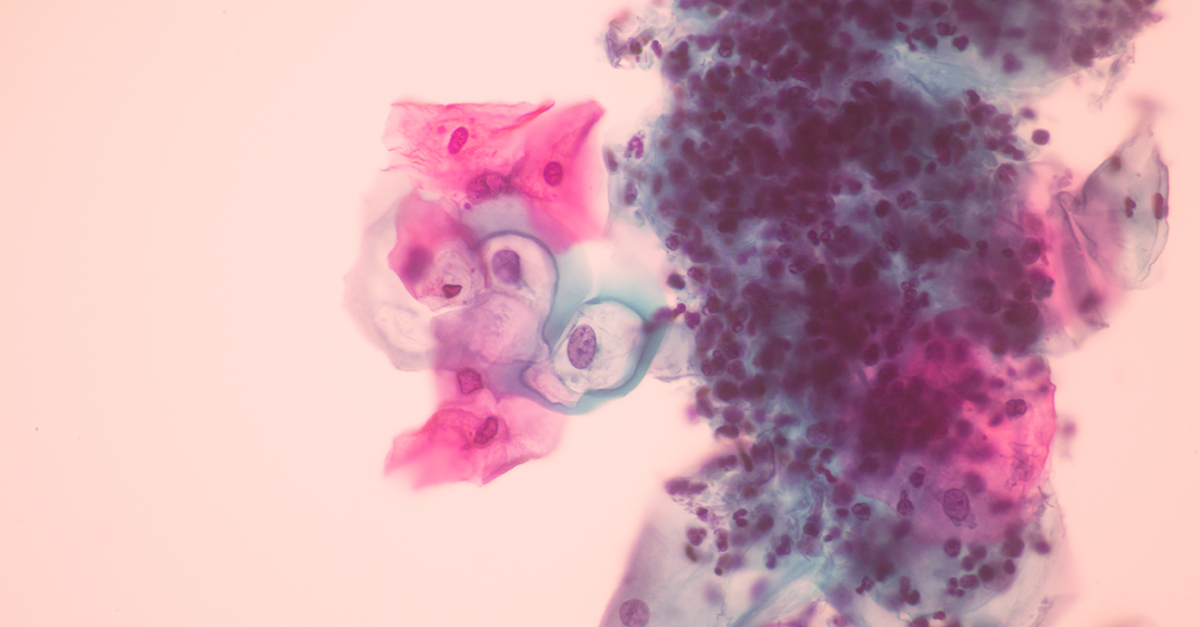

A 2022 study published in the journal Nature Communications indicated that cervical cell samples collected during a Pap smear may be able to predict ovarian cancer risk.

"The study describes how a collection of cells from the uterine cervical area, much like what is done during a routine Pap smear, can be used to find or predict the risk of developing ovarian cancer," explained Steven Vasilev, M.D., a quadruple-board-certified integrative gynecologic oncologist, medical director of integrative gynecologic oncology at Providence Saint John's Health Center and professor at Saint John's Cancer Institute in Santa Monica, California.

The cells are collected using a brush from the cervical area but can originate from anywhere in the Müllerian (gynecological organ) tract or ducts, which includes the cervix, uterus, ovaries and fallopian tubes, Vasilev explained.